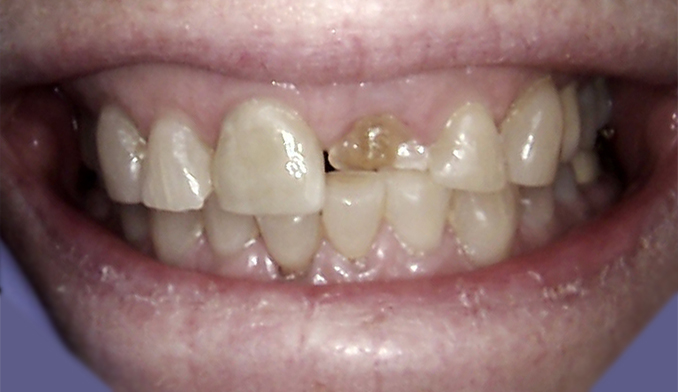

Immediate Implant Placement After Front Tooth Loss

The patient presented with a broken front tooth that could not be saved. We removed the tooth and immediately placed a dental implant to preserve the natural appearance. After four months of healing, a custom implant crown was placed, fully restoring the patient’s smile and function.